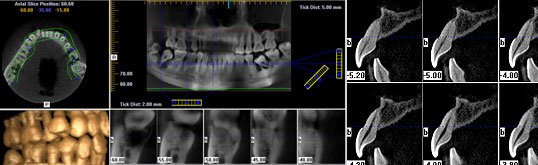

Eine DVT führen wir vor Implantationen und anderen oralchirurgischen Eingriffen durch, wenn herkömmliche Röntgenverfahren nicht die notwendigen Informationen liefern. Beispielsweise ist der Unterkiefernerv auf üblichen Röntgenaufnahmen nicht immer ganz zu sehen, da diese nur eine zweidimensionale Darstellung des Kiefers und der Zähne ermöglichen. Daher kann der Nerv von anderen Bereichen überdeckt werden.

Mit der DVT hingegen können wir…

• den Verlauf des Unterkiefernervs durchgängig nachvollziehen,

• vor einer Implantation die Höhe und Dichte des Kieferknochens exakt bestimmen,

• im Kiefer verbliebene ("verlagerte") Weisheitszähne sehr gut erkennen.

Die DVT-Aufnahmen setzen wir für die computergestützte dreidimensionale Planung ein.